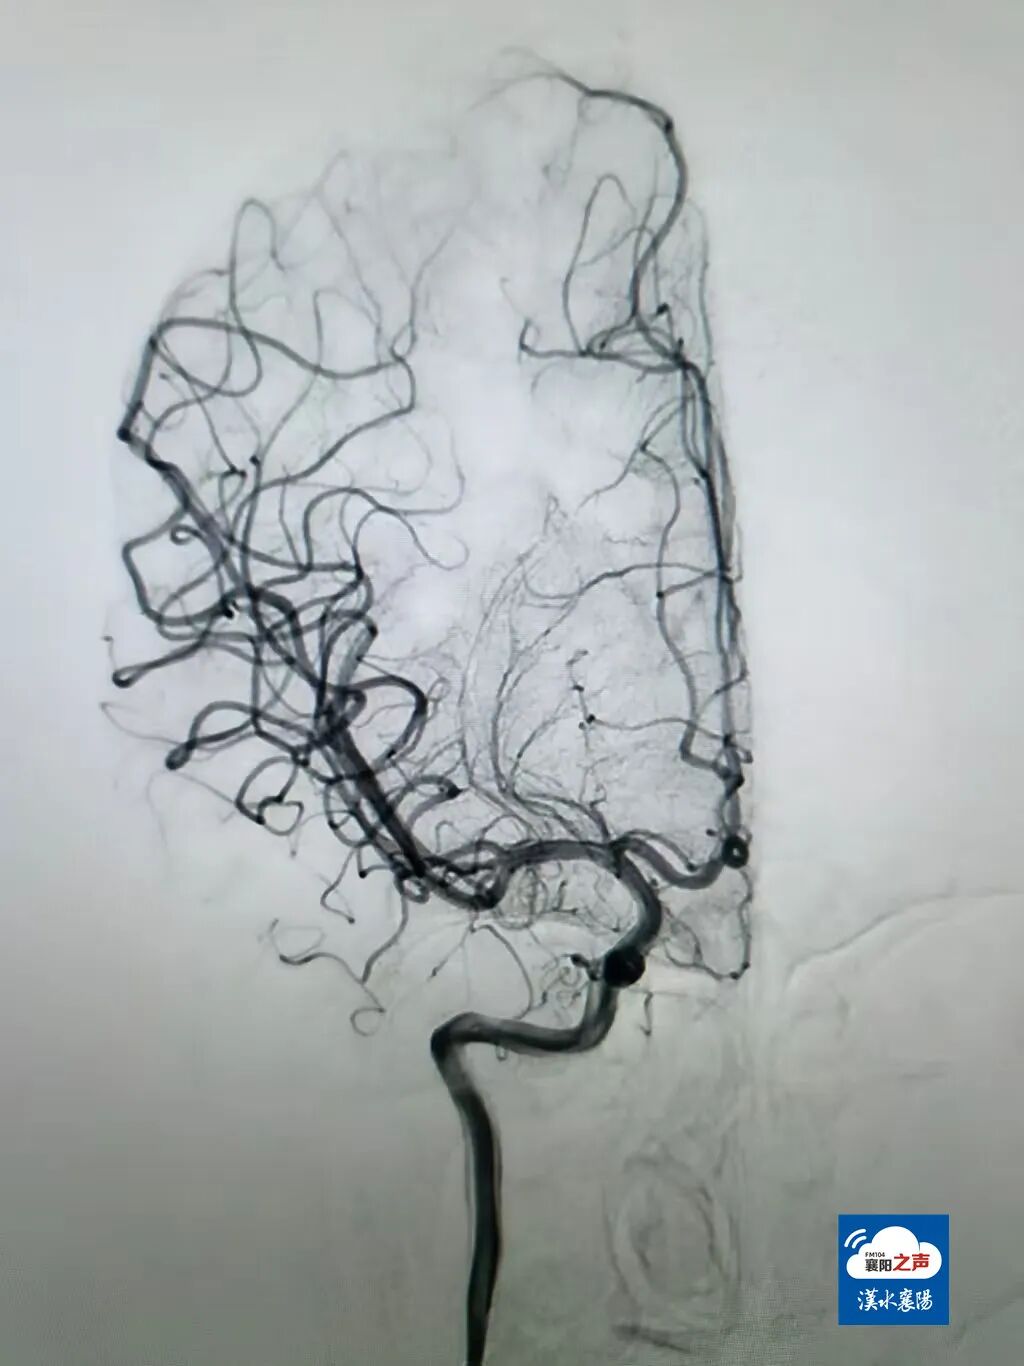

近日,19岁大学生(小李)凌晨上厕所时,突感左侧肢体无力、无法活动,被老师和室友紧急送到襄阳市中医医院急诊科。经检查,小李右侧大脑中血管闭塞。治疗团队立即实施机械取栓术,成功将堵塞血管的血栓完整取出。